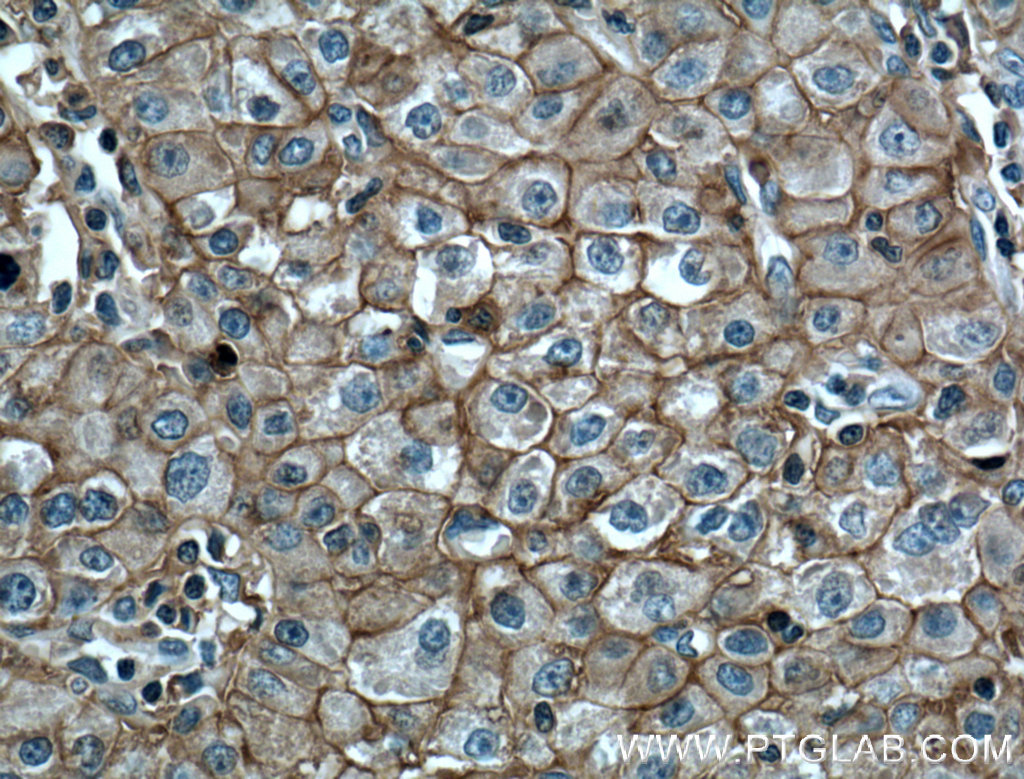

| Positive IHC detected in | human liver cancer tissue, human placenta tissue, human tonsillitis tissue Note: suggested antigen retrieval with TE buffer pH 9.0; (*) Alternatively, antigen retrieval may be performed with citrate buffer pH 6.0 |

| Immunohistochemistry (IHC) | IHC : 1:50-1:500 |

66443-1-Ig targets CD147 in WB, IHC, IF/ICC, IF-P, IP, ELISA applications and shows reactivity with human, pig samples.

CD147, also known as Basigin or extracellular matrix metalloproteinase inducer (EMMPRIN), is a transmembrane glycoprotein that belongs to the immunoglobulin superfamily (PMID: 7812975). The molecule is composed of an intracellular portion, an extracellular portion and a single transmembrane region. CD147 is expressed on a variety of cell types (e.g., hematopoietic, epithelial, and endothelial cells) and at varying levels (PMID: 32968061). Increased expression of CD147 occurs in many tumors. CD147 is a pleiotropic molecule that plays an important role in fetal, neuronal, lymphocyte and extracellular matrix development (PMID: 17945211). CD147 has been identified as a receptor essential for erythrocyte invasion by Plasmodium falciparum (PMID: 22080952). It has been reported that spike protein of SARS-CoV-2 binds to CD147 on host cells, thereby mediating the viral invasion (Wang, Ke, et al, BioRxiv, 2020). The CD147 gene, designated BSG for basigin, is located on chromosome 19p13.3. Four transcript variants encoding different isoforms have been found (PMID: 21536654). CD147 migrates on SDS-PAGE usually between 35 and 65 kDa, depending on the degree of glycosylation (PMID: 17945211).